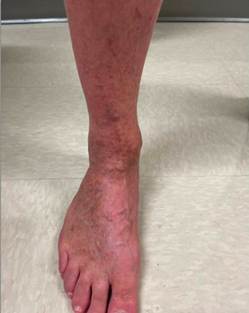

A 56-year-old male furniture designer presented with long-standing bilateral lower extremity discoloration, swelling, aching, pain, and throbbing (Figures 1A and 1B). His symptoms had been present for many years and were exacerbated by prolonged standing for several hours daily as part of his occupation. He had consistently worn graduated compression stockings without meaningful symptomatic relief.

Figures 1A (Left) and 1B (Right): Lower leg hyperpigmentation prior to great saphenous vein ablation.